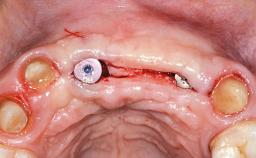

This 20-year-old woman was referred to our department in July 2006. Four months earlier, she had experienced dental trauma to the anterior maxilla when traveling in South America. The emergency treatment included emergency root canal treatment of teeth 12 and 11. Tooth 21 was also subjected to endodontic treatment later. At the initial examination, the patient was not in pain but reported increased mobility of tooth 12. The clinical examination revealed a high smile line, medium thickness of the soft tissue, and rectangular tooth forms. Discoloration of tooth 12 was evident. The periapical radiograph provided by the referring dentist indicated a fracture line at both teeth 12 and 11. A cone-beam computed tomography (CBCT) scan confirmed these fractures. No pathology was found to be associated with tooth 21.